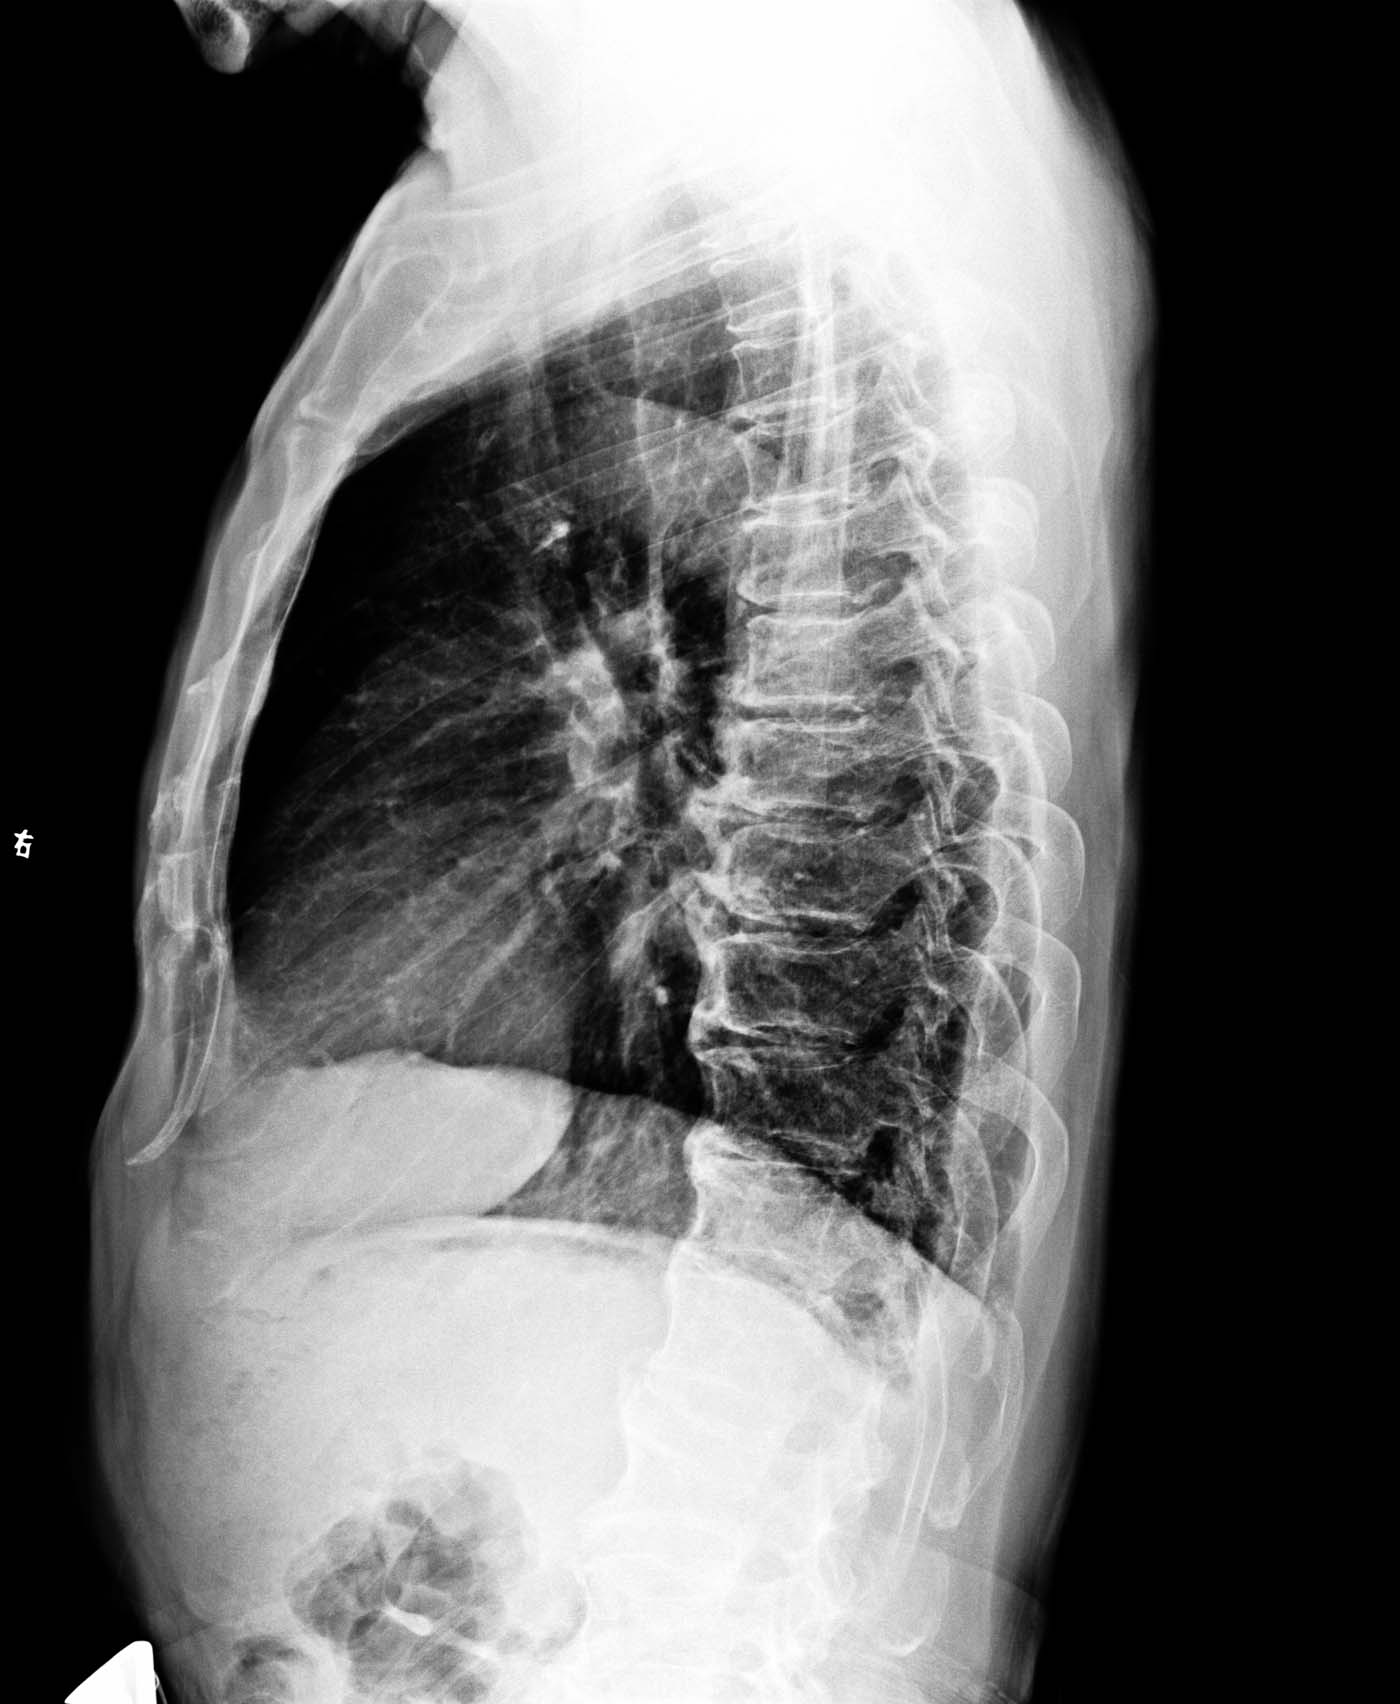

标题: X2088:右下肺背段囊性?空洞?

男,46岁,有咳嗽,无咯血,无发热。右下肺背段见一大小约1.5*1.5cm囊肿?还是空洞?,其内未见液平面,右下肺另见索条状密度增高影。

胸椎退变

胸椎退行性骨关节病。建议ct检查除外肺部病变。

胸透发现右下肺囊状影或空洞影后进行摄片的。

右下肺看到条索状阴影,有没有空洞好像不怎么肯定,建议ct检查吧